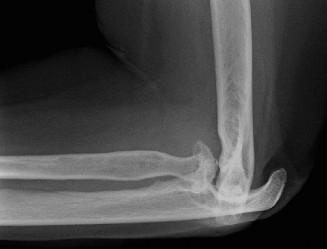

Treat a patient with infected total shoulder arthroplasty? CASE 21 A 70-year-old, right-hand-dominant female presents to clinic complaining of 4 years of gradually worsening chronic right shoulder pain and stiffness. She says the pain is worse at night and with any range of motion, denies a history of trauma, pain in other extremities, or numbness or tingling of the right upper extremity. She notes that her mother suffered from rheumatoid arthritis that affected her shoulder. Physical examination reveals decreased muscle bulk over the right supra- and infraspinatus fossae compared to the contralateral side, limited active and passive ROM, marked weakness with external rotation, and 4+/5 strength with shoulder abduction. X-rays of the right shoulder are shown in Figures 2–58 and 2–59.

Figure 2–58

Figure 2–59

The correct answer is (C). Rotator cuff tear arthropathy consists of a combination of rotator cuff insufficiency, glenohumeral joint degenerative changes, and superior humeral head migration. It is more common in women and also more often found on the dominant side. The patient’s clinical examination with weakened external

rotation and muscle atrophy signaling incompetent supra- and infraspinatus muscles point to rotator cuff insufficiency, and her plain films reveal narrowed glenohumeral joint space as well as superior migration of the humeral head. Choice D is incorrect because, while radiographs would show narrowing of the glenohumeral joint space, they would also likely show numerous osteophytes and posterior wear of the glenoid. Choice B is incorrect because, while adhesive capsulitis does present as decreased active and passive range of motion, the patient’s constellation of symptoms pointing towards rotator cuff insufficiency along with the radiographs make cuff tear arthropathy the more likely choice. Finally, Choice A is incorrect because even though she has a positive family history of rheumatoid arthritis, it is less likely to present only in a single joint. Also, rheumatoid arthritis on radiography appears more as an erosive process without the characteristic superior migration of the humeral head.

Which of the patient’s radiographic findings is most indicative of chronic rotator cuff insufficiency?

- Superior migration of the humeral head

The correct answer is (A). Superior migration of the humeral head would be most indicative of chronic rotator cuff insufficiency associated with cuff tear arthropathy, as it is a direct result of the inability of the rotator cuff tendons to help maintain the humerus in its normal position. Acetabularization of the undersurface of the acromion is commonly associated with superior migration of the humeral head found in rotator cuff tear arthropathy, and can be assessed using the Hamada classification, which is based on measurements of the acromiohumeral interval on radiography (Table 2–8). Choices B and C are incorrect because, while narrowed glenohumeral joint space and subchondral sclerosis are associated with rotator cuff arthropathy on radiographs, they indicate degenerative joint changes rather than chronic rotator cuff insufficiency. Choice D is incorrect because it is not a specific sign of rotator cuff arthropathy.